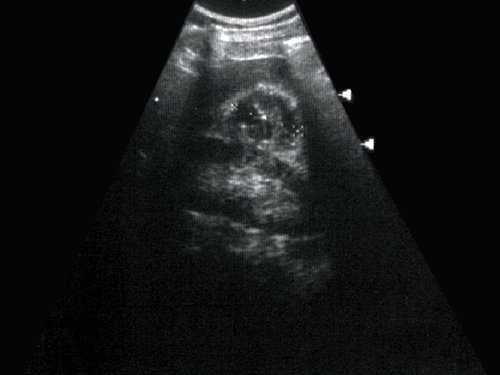

Рис. 1. Эхограмма. Кистозное образование правой почки. Гистологически - почечно-клеточная кистозная карцинома.

Многокамерное образование неправильной формы, с неровной толстой стенкой, с вкраплениями кальция, множественные перегородки с локальными утолщениями. Выраженная неоднородность внутренней эхоструктуры в виде чередования гипо-, изо- и гиперэхогеных участков.